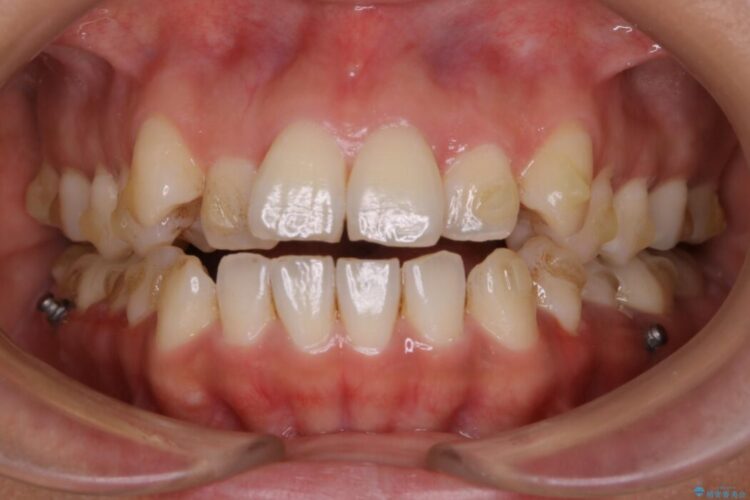

治療後について

きちんと装着時間を守っていただいたこともあり、きれいな歯並びを獲得できました。

マウスピースとマイクロインプラントの併用により矯正するための隙間を確保し、治療期間は長くなりますが非抜歯できれいな歯列弓を得ることができます。